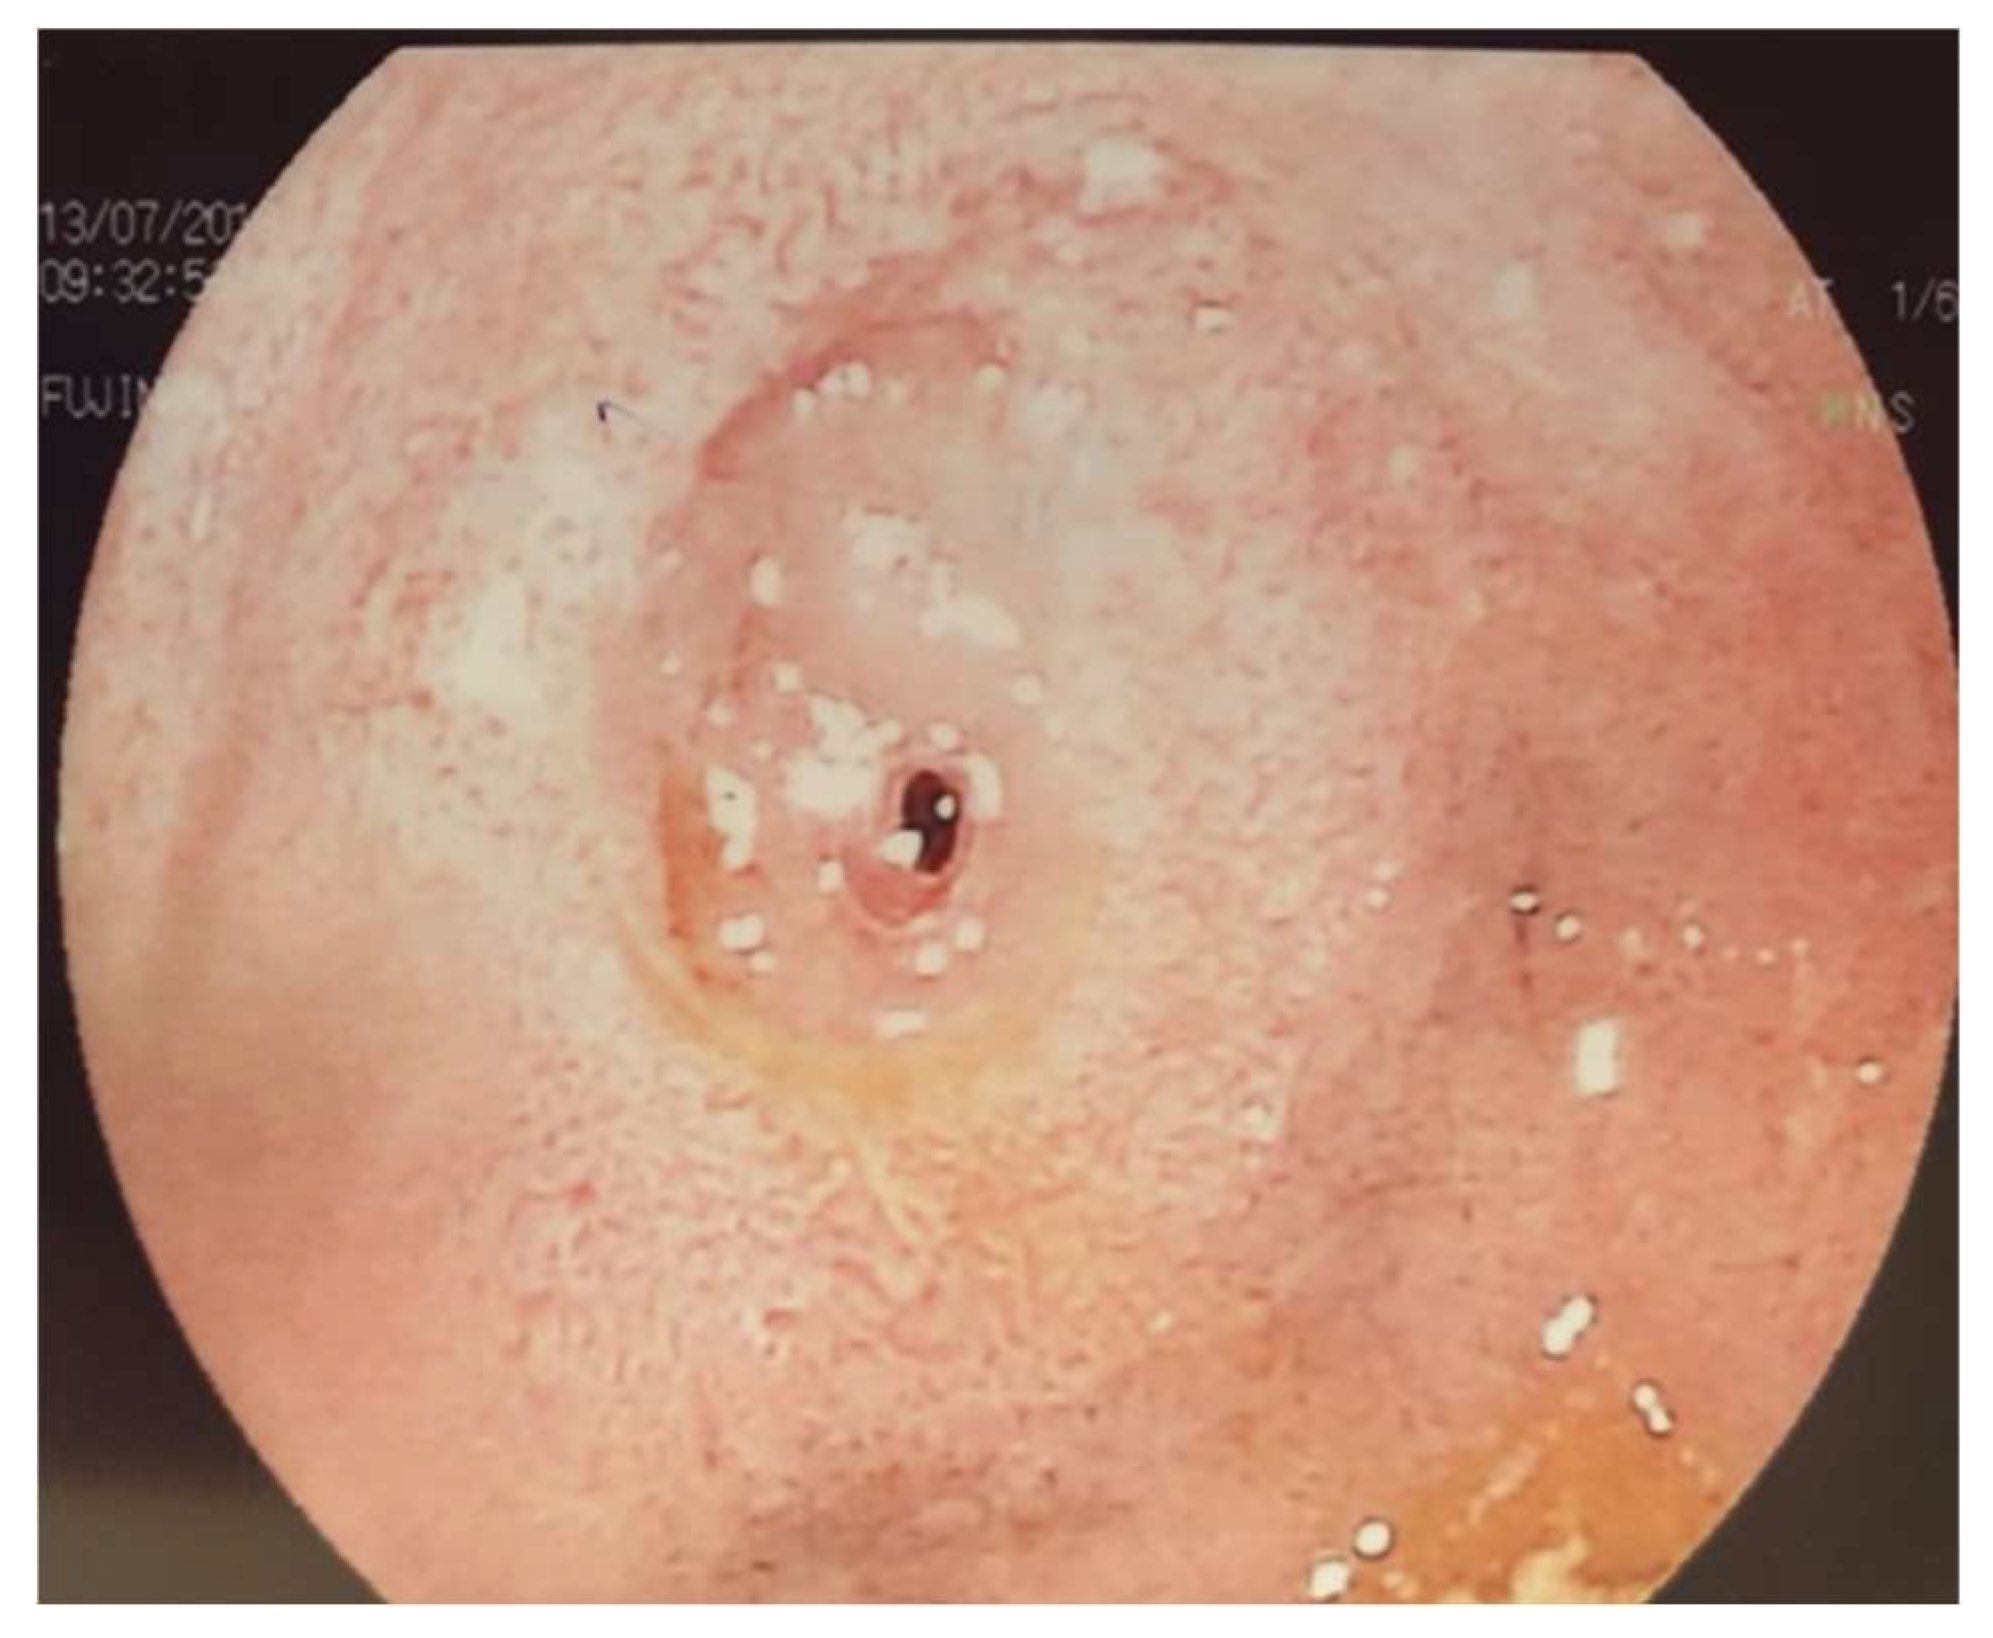

2. Case Presentation